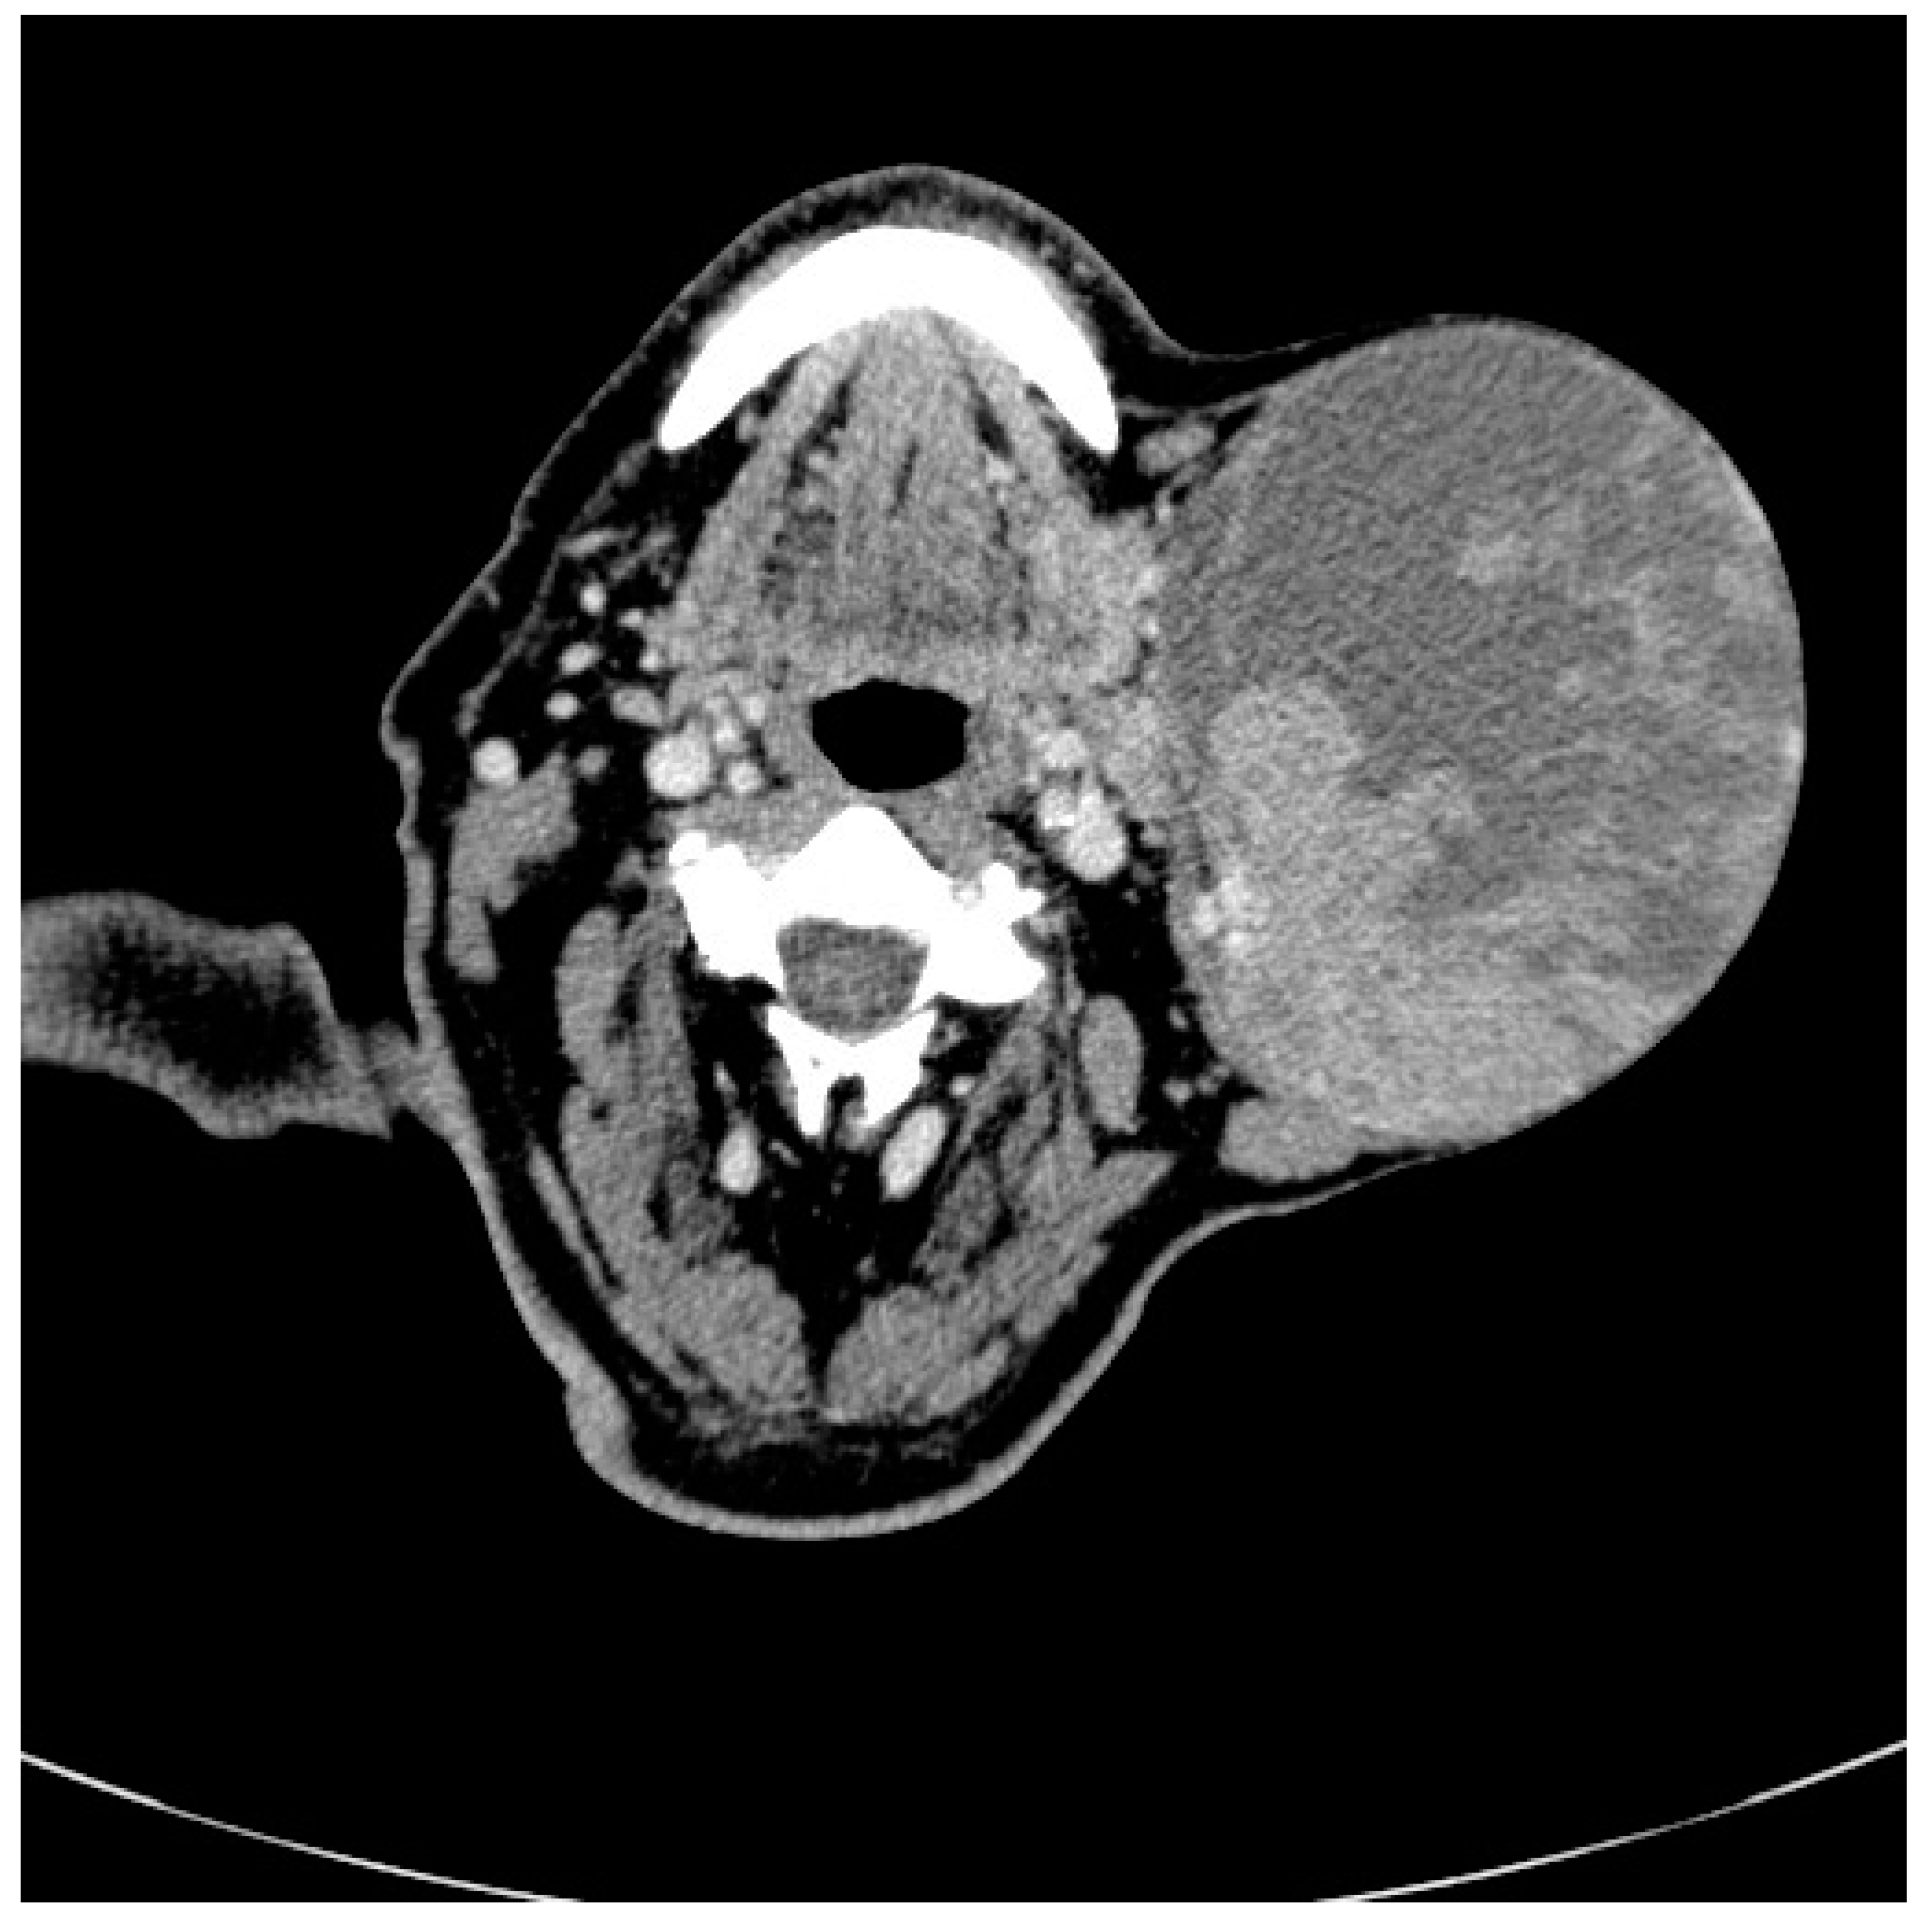

2. Case Presentation